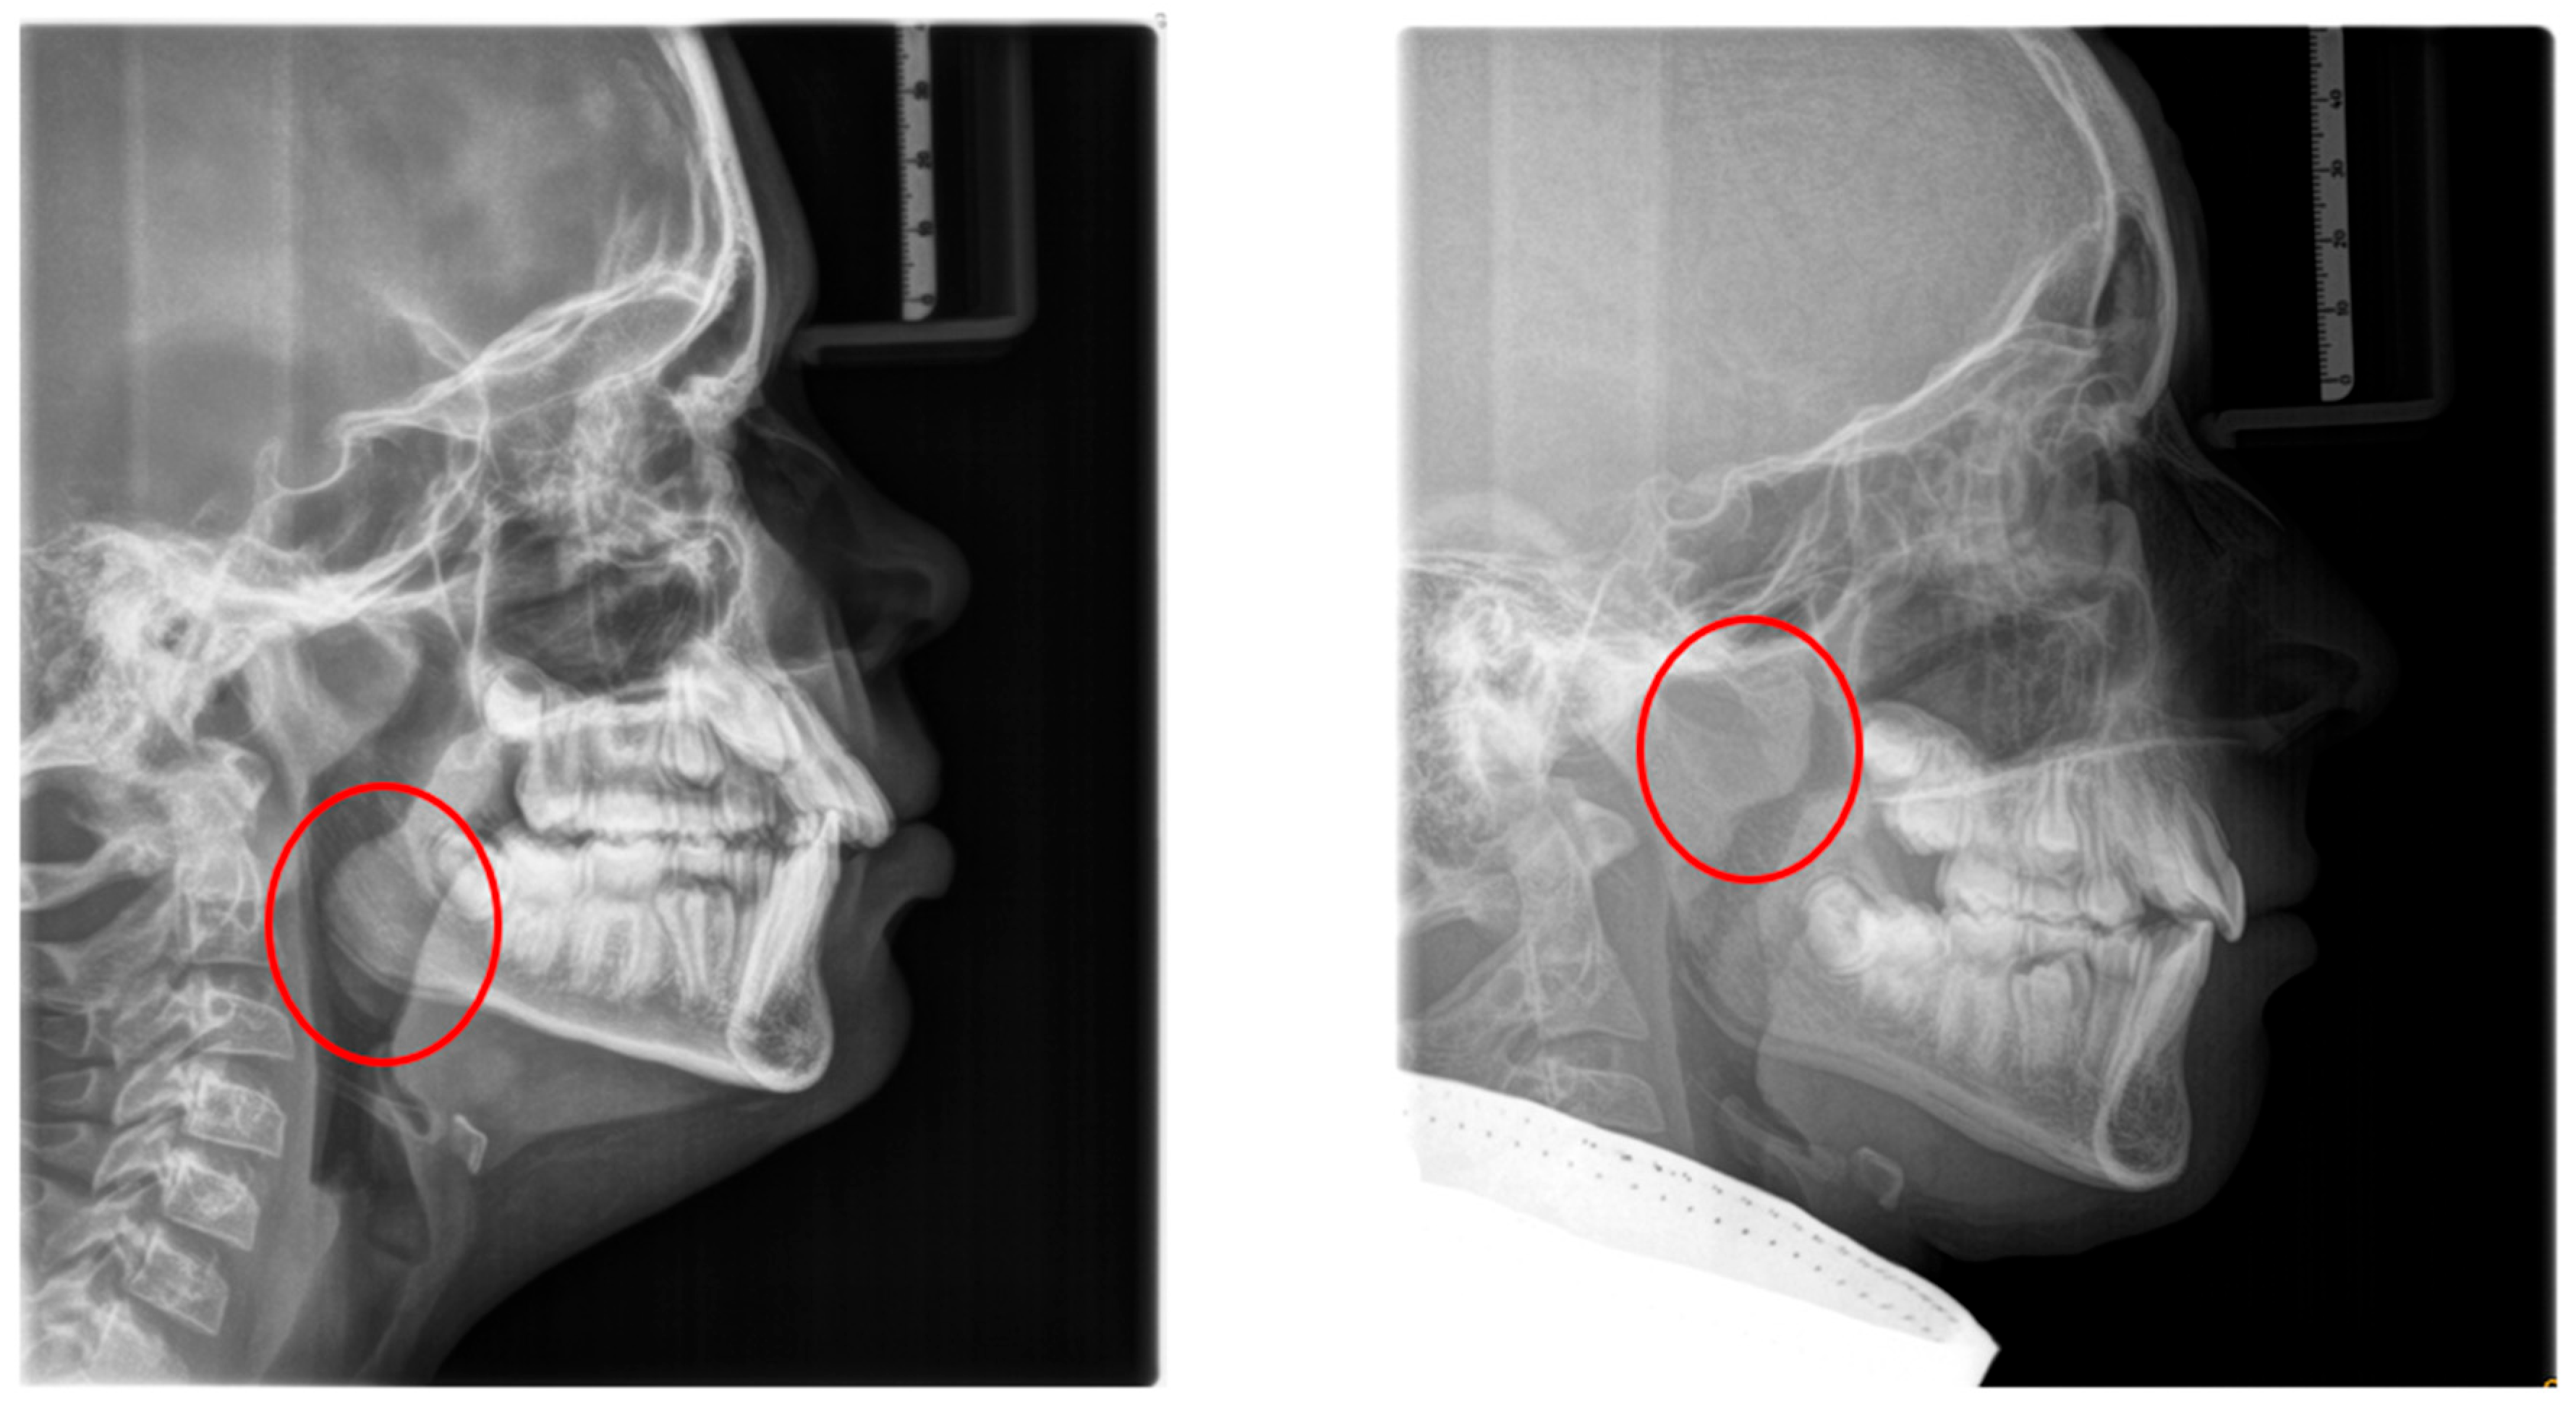

These patients often exhibit “adenoid facies” characteristics and present with dark circles around the eyes, flattened cheekbones, dry lips, an open-mouth posture, a lowered mandibular posture, a low tongue position, labial incompetence, underdeveloped nasal bones, pronounced nasolabial furrows, which collectively complete the typical appearance [57,61,69,70,71]. They often present a convex profile due to a retrognathic mandible (Figure 4) and an increased mandibular angle. The lower facial third is frequently longer than the average (long-face, dolichofacial morphology) [69] (Table 2). Additionally, they exhibit an altered head position resulting from hyperextension of the cervical spine and an overall reduction in orofacial muscle tonicity.

Lateral cephalometry allows for systematic assessment of craniofacial structures, including both hard and soft tissues. Furthermore, it enables the evaluation of the sagittal dimension of the posterior airway space (PAS) and can therefore serve as a screening tool [101,102]. This diagnostic tool is reproducible, affordable, easily accessible in an orthodontic office, involves minimal radiation exposure, and is non-invasive [2] (Figure 6). The cephalometric radiographs are taken in an upright and natural head position, where the eyes focus ahead with a horizontal visual axis parallel to the floor (Frankfort horizontal plane). The occlusion should be the habitual bite (not forced into maximum intercuspation) and the lips in gentle contact (not forcefully closed).

Nevertheless, it is essential to note that the soft tissues in the upper airway behave differently when a person is asleep, in a supine position, compared to an upright position [103,104,105,106]. Several studies attempted to establish a relation between airway dimensions and craniofacial structures in subjects with OSA through cephalometric assessment [107,108,109].